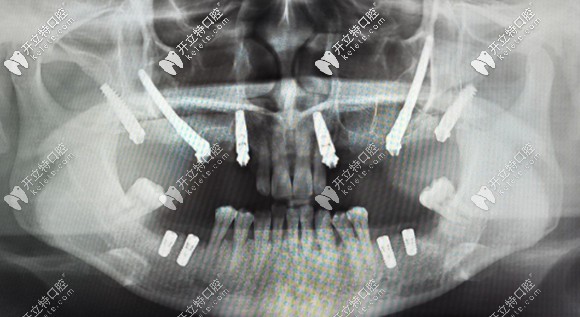

例如:術(shù)前采用專(zhuān)用軟件,結(jié)合患者口腔數(shù)據(jù),對(duì)種植方案進(jìn)行詳細(xì)手術(shù)設(shè)計(jì)。

采用3D打印患者上頜骨模型,在模型上先進(jìn)行摸擬手術(shù)。

制作手術(shù)導(dǎo)板,以便于在手術(shù)中進(jìn)行定點(diǎn)指導(dǎo)等措施。

做好術(shù)前準(zhǔn)備可避免穿顴穿翼種植并發(fā)癥的發(fā)生

正常情況,患者若身體條件許可,該種植技術(shù)是無(wú)需住院,無(wú)需全麻,也無(wú)需靜脈給藥鎮(zhèn)靜,在常規(guī)局部麻醉下就能進(jìn)行。

而且是局部小翻瓣,避免大翻瓣的創(chuàng)傷及術(shù)后較重的腫脹疼痛反應(yīng)。穿翼種植更是不翻瓣種植,術(shù)后即刻修復(fù),快速恢復(fù)咬合功能。

還可以消除對(duì)骨移植的需求,省去上頜竇提升手術(shù),縮短療程。